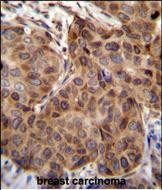

| IHC | 1/100-1/500 | Human,Mouse,Rat |